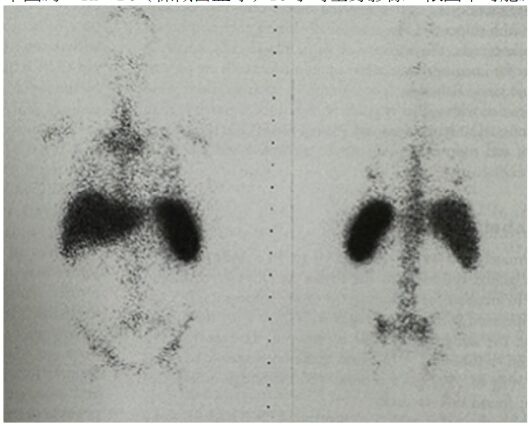

45.下圖為 (標幟白血球)18 小時全身影像小時全身影像,依圖示可能為下列何種疾病?

(A)正常分布情況 (B)腹膜炎 (C)肝臟與脾臟膿瘍 (D)克隆氏症(Crohn's disease)